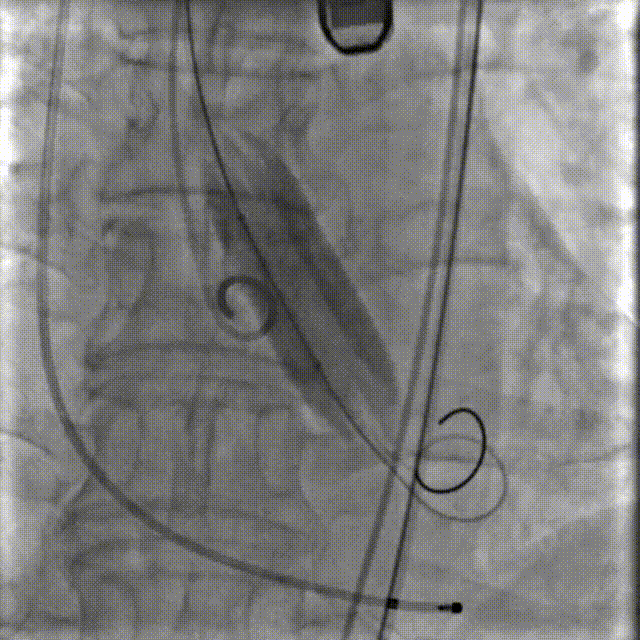

李有金教授 宁夏回族自治区人民医院 “随着人口老龄化加剧,主动脉瓣狭窄患者数量逐年增多,其中高龄、合并多种基础疾病的复杂病例占比不断提升。经导管主动脉瓣置换术(TAVR)作为微创治疗技术,已成为此类患者的重要治疗选择。对于高龄、有恶性肿瘤病史的患者而言,手术的安全性、微创性与长期疗效同等重要,既要最大程度降低手术创伤与并发症风险,也要确保瓣膜的耐用性与患者术后生活质量。 全球首款预装干瓣ProStyle A®的临床应用,为复杂病例治疗提供了全新解决方案。该瓣膜无需术中戊二醛冲洗,大幅缩短了手术操作时间,尤其适合高龄、心功能欠佳的患者。其独特的抗钙化工艺与优化的瓣架设计,既保证了瓣膜的长期耐久性,又能有效规避冠脉风险,为患者的“全生命周期管理”奠定了坚实基础。” 病例简介 现病史:患者半月余前突发抬头时一过性头晕,持续数秒钟,每日发作3-5 次,伴天旋地转感,症状可自行缓解。2025年12月12日就诊于外医院,心脏彩超提示“主动脉瓣狭窄(重度)并关闭不全(轻度),左室壁增厚,升主动脉增宽,左心室收缩功能正常,舒张功能减退”,建议转上级医院诊治。为求进一步治疗,患者就诊我院,门诊以“主动脉瓣狭窄”收住入院。 既往史:胃癌,胃大部切除术后五年。 临床诊断:“1.主动脉瓣狭窄伴有关闭不全(重度狭窄伴轻度关闭不全);2.主动脉瓣钙化;3.肥厚性非梗阻性心肌病;4.心功能不全;心功能III级(NYHA分级);5.升主动脉扩张;6.胃恶性肿瘤个人史” 术前CT评估显示:Type-1型二叶瓣,R-N钙化粘连,瓣叶重度钙化,主要分布在无冠窦瓣叶游离缘、R-N对合缘粘连处及右冠窦基底部;钙化积分933.2mm³;主动脉瓣环直径26mm,LVOT 27.6mm;双侧瓣叶开口高度可,左冠开口高度22.0mm,右冠开口高度20.0mm;主动脉水平夹角57.7°,左室内径偏小;主动脉弓部75.1°锐角弓;外周入路无明显迂曲及钙化,双侧股动脉内径可,右股中分叉。 手术策略 右侧股动脉为主入路,左侧为辅助入路,20F大鞘,股骨头中段穿刺;预装金仕生物 ProStyle A® AV26瓣膜,备29瓣膜,22mm球囊预扩;初始定位对齐瓣环上5mm超高位释放,释放过程中使瓣膜自然下滑至工作位,最终理想位置零位,利用瓣上锚定与封堵,规避冠脉风险;术前适当补液; 手术过程 Step1:主动脉根部造影; 主动脉根部造影 Step2:使用“先瑞达”22mm球囊预扩,无腰无漏,冠脉充盈良好; 球囊预扩 Step3:将ProStyle A®预装干瓣送至目标位置,初始定位后缓慢释放,观察瓣膜自然下滑至理想工作位; 定位 释放至工作位观察 Step5:瓣膜完全释放后,再次造影,显示瓣膜位置、形态良好,导管测平均跨瓣压差由术前60mmHg-降至1mmHg,冠脉血供正常; 最终造影 Step6:术后即刻超声监测,人工瓣膜位置固定,瓣叶启闭无受限,瓣周少量反流。 术后患者病情稳定,已于一周后出院。 结语 作为宁夏回族自治区心血管疾病诊疗的核心高地与区域医疗中心建设的标杆单位,宁夏回族自治区人民医院始终坚守“敬佑生命、救死扶伤”的医者初心,以“技术引领、学科兴院”为发展理念,在心脏大血管领域持续深耕,构建了集“精准评估-个性化方案-微创治疗-全程康复”于一体的诊疗体系。此次西北首例ProStyle A®预装干瓣植入手术的圆满成功,不仅是医院在复杂结构性心脏病介入治疗领域的又一突破性成果,更彰显了医院在引进前沿技术、转化创新器械、服务复杂重症患者方面的责任与担当。 Prostyle A®预装干瓣——助力临床最优化解决方案: 预装干瓣 便捷顺安:金仕生物专利抗钙化技术运用纳米技术去除组织内的细胞碎片和磷脂,封闭游离醛基,从根本上阻断了瓣膜钙化的多项因素,显著提升了瓣膜的耐久性;同时,相比较传统戊二醛保存方式,干式存储最大限度的保留心包的亲水亲油平衡,还原组织天然曲柔性,进一步保障了瓣叶开合,保证长期耐久性; 平衡径向支撑力:Prostyle A®瓣架网孔比例按照病例解剖结构的特殊设计,使瓣膜在狭窄最重的地方良好的撑开,同时避免对瓣环及周边组织的过度压迫,有效降低传导阻滞风险; 精准释放:底部桶状设计更易迅速锚定,协同释放张力小,助力最终精准释放; 过弓柔顺:较细的输送系统直径+亲水涂层,显著提升输送系统通过性,有效减少血管并发症的发生,内连鞘版本最小尺寸等效14F大鞘; 专家简介 李有金 宁夏回族自治区人民医院(点击查看专家详细简历) · END ·